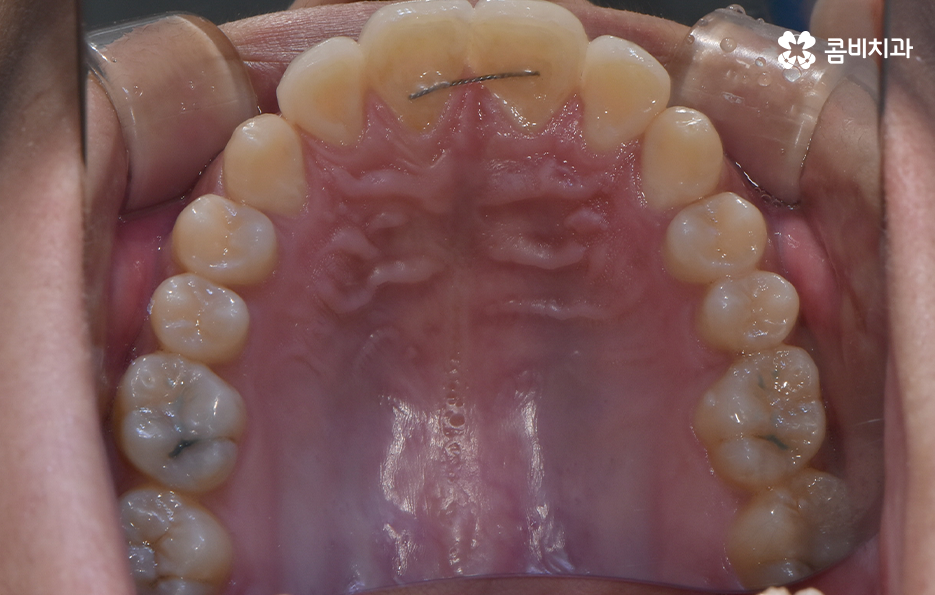

과잉치 중에서는 어떤 치아가 과잉치인지 구분이 어려울 정도로 일반적인 정상 치아의 크기와 비슷한 크기와 형태를 띄는 경우도 있는 반면에 위 사진의 케이스는 첫번째 앞니와 앞니 사이에 유독 작은 왜소치가 있는 형태이기 때문에 치아의 기능적인 문제 보다는 심미적인 개선을 필요했던 케이스로 볼 수 있어요

그나마 다행인 점은 앞니만교정을 하더라도 치아의 교합이나 골격적인 부분, 얼굴형 등에 있어서 큰 지장은 없던 경우였는데요. 물론 아랫니가 다소 벌어져 있기 때문에 전체교정을 하면 더 좋은 결과를 얻을 수 있었겠지만 환자분의 니즈에 있어서 앞니만교정을 빠르게 원했던 사례이기 때문에 앞니 부분의 과잉치 발치 후 앞니만교정을 부분적으로 진행했어요

과잉치로 인해 말그대로 치아의 정상 범위 이상으로 치아가 배열되기 때문에 다른 치아의 배열에도 악영향을 주는 경우가 많지만 위 환자분의 케이스의 경우에는 치열 자체는 전체적으로 가지런한 편이라는 점과 특히 턱뼈가 넓은 편이라는 점에서 전체교정을 하지 않았어도 환자분이 원하는 치료의 목표는 달성할 수 있었어요

치아교정 기간은 각 환자분들에 따라 천차만별이기 때문에 정확하게는 각 환자분들의 상태를 직접 확인해봐야 하며 누구나 앞니만 부분적으로 교정이 가능한 것은 아니기 때문에 정밀검진이 우선적으로 필요하며 위 환자분의 경우에는 과잉치를 발치하고 교정기 장착 후에 약 6개월 정도가 지나서 교정기를 떼어낼 수 있었어요